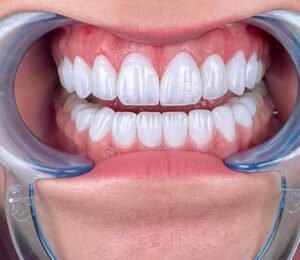

Cận cảnh cấy ghép Implant – Công nghệ phục hình răng hàng đầu hiện nay

Sau khi trụ Implant tích hợp chắc chắn với xương hàm, bác sĩ sẽ gắn mão răng sứ lên trên để tạo thành chiếc răng hoàn chỉnh, có hình dáng và chức năng tương tự răng thật.

- Thẩm mỹ cao: Răng Implant có màu sắc, hình dáng giống răng thật